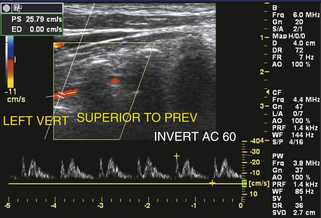

Часто в случаях подключичного обкрадывания может возникнуть обструкция подключичной артерии в ее начале, гемодинамически значимая, но не настолько тяжелая, чтобы вызвать полное изменение кровотока в ипсилатеральной позвоночной артерии. Изменение баланса гемодинамических сил во время сердечного цикла вызывает замедление систолического кровотока в позвоночной артерии ( рис. 11-12 ), которое, если оно достаточно сильное, проявляется как двунаправленный поток ( рис. 11-13 ). Во время пиковой систолы происходит значительное падение давления на стенозе подключичной артерии в связи с высокоскоростной струей потока. В то же время в контралатеральной позвоночной артерии и основной артерии присутствует нормальное систолическое давление. В результате возникает чистый градиент давления от дистального к проксимальному поперек позвоночной артерии на стороне подключичного стеноза, что вызывает замедление во время систолы или даже временное изменение направления кровотока. Во время диастолической фазы сердечного цикла скорость кровотока в пораженной подключичной артерии снижается и значительного падения давления в месте стеноза не происходит; таким образом, во время диастолы чистый градиент давления внутри пораженной позвоночной артерии по существу нормальный и обеспечивает антеградный поток с уменьшенной абсолютной скоростью потока.

РИСУНОК 11-13. Аномалии формы позвоночных волн, ипсилатеральные по отношению к прогрессирующему обкрадению подключичной мышцы. Этот спектральный допплеровский сигнал показывает двунаправленный поток. В этом случае стеноз подключичной артерии достаточно серьезен, чтобы вызвать временное изменение направления кровотока во время пиковой систолы с уменьшенным, но антеградным потоком во время диастолы.

Когда баланс гемодинамических сил создает двунаправленный характер потока, общий эффект представляет собой чистый объемный кровоток в позвоночной артерии, который очень мал, порядка нескольких миллилитров в минуту. Этот чистый поток может быть как антеградным, так и ретроградным, а ангиографически низкая скорость потока может привести к невизуализации позвоночной артерии, имитируя окклюзию. 17